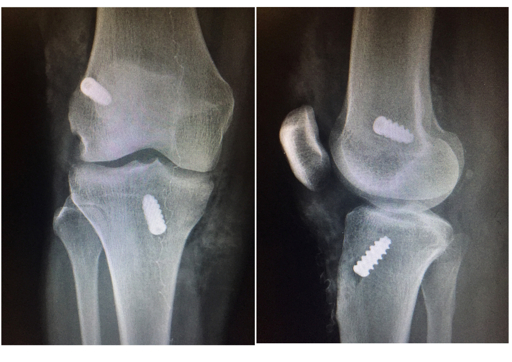

Exames de Imagem: Ressonância e Radiografia

A radiografia simples não mostra os ligamentos diretamente, mas é importante para descartar fraturas associadas. Em traumas mais intensos, pode haver arrancamento ósseo no local de inserção do ligamento, e a radiografia identifica essa situação.

Em alguns casos, a tomografia computadorizada pode ser solicitada para avaliar detalhes ósseos com maior precisão. Isso é especialmente útil no planejamento cirúrgico, quando o cirurgião precisa saber exatamente o formato e as dimensões dos túneis ósseos.

Os remanescentes do ligamento rompido são removidos para preparar o espaço onde o novo enxerto será posicionado. Em seguida, o cirurgião perfura túneis no fêmur e na tíbia, exatamente nos pontos de origem e inserção do LCA original. A precisão no posicionamento desses túneis é um dos fatores mais críticos para o sucesso da cirurgia.

Finalmente, o enxerto é fixado nos túneis ósseos com implantes específicos, que podem ser parafusos de interferência, botões corticais ou outros dispositivos. As incisões são fechadas com pontos e curativos impermeáveis são aplicados.